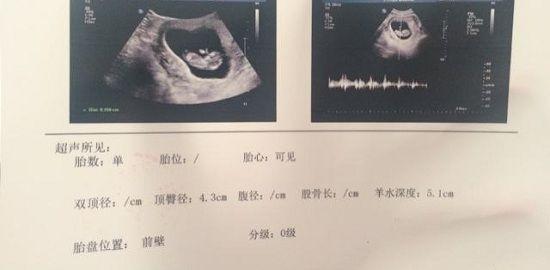

nt检查报告图一览

nt检查正常值一般是在≤2.5mm,只要通过nt检查发现nt值在正常值范围内,就可不用担心了,nt检查属于一次检查。